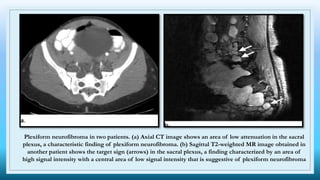

Plexiform neurofibroma in two patients. (a) Axial CT image shows an area of low attenuation in the sacral

plexus, a characteristic finding of plexiform neurofibroma. (b) Sagittal T2-weighted MR image obtained in

another patient shows the target sign (arrows) in the sacral plexus, a finding characterized by an area of

high signal intensity with a central area of low signal intensity that is suggestive of plexiform neurofibroma

Imaging

 CT –

o well-defined hypodense mass low attenuation lower than that in adjacent soft tissues

o minimal or no contrast enhancement

o may resemble lymphadenopathy

 MRI –

o T1: hypointense

o T2 : hyperintense

■ target sign

● a hyperintense rim (myxoid material ) and central area of a low signal (dense

central area of collagenous stroma ) may be seen

● although this sign is highly suggestive of neurofibroma, it is occasionally also

seen in schwannomas and malignant peripheral nerve sheath tumors

■ fascicular sign

o T1 C+ (Gd): heterogeneous enhancement